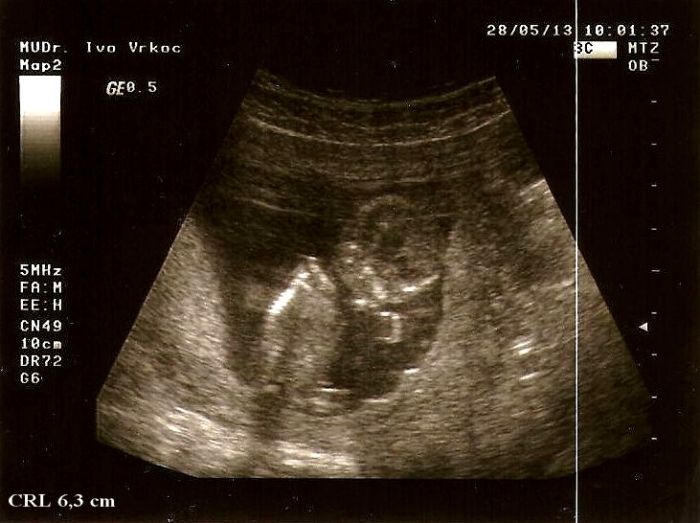

Tak jsme doma z prvotrim. screeningu a jsme už straašně velicí..

Teda oproti tomu co naměřil v úterý můj dr. jsme o několik dní větší..

Pak ho trošku poškádlila, tak zaujal normální polohu a mohli jsme měřit. CRL máme 7,26cm a odpovídáme 13+3tt, projasnění bylo 1,3, takže prý v pořádku a stehenní kostička meřila 1 cm..Dr.mi všechno krásně popisovala a přibližovala, hlavně na obličejíčku a mrňous u toho sebou aktivně mrskal a ukazoval nám jak má dlouhý nožičky a pak se dr. smála a říká,,a teď si cpe ručičky do pusinky''..

Přikládám 3 otečky mrňouska,první je z kontroly u mého dr.jak tam hačá,na té další se musím smát jak ukazuje chodidlo a druhou nohou se snaží prokopnout ven z bříška